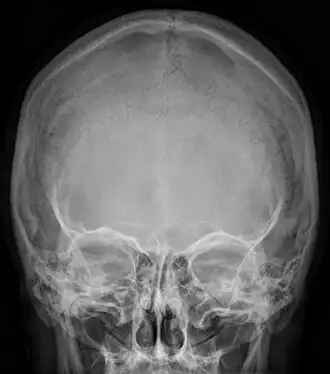

Radiograph of the skull showing an interparietal bone between the occiput and parietal bones

In humans, it corresponds to the upper portion of the squama of the occipital bone that lies superior to the highest nuchal line and is completely fused to the supraoccipital. However, in some individuals this portion remains separate from the rest of the occipital bone throughout life. In such cases, this separate bone is particularly referred as Inca bone. Inca bones in humans were first found in the skulls of contemporary indigenous peoples of the southern Andes as well as in those of mummies of the Inca civilization. Although the Inca bone was originally encountered as a variation in South American and Latin American cranial remains, the variation occurs in people from all geographic regions of the world and is by no means indicative of South/Latin American origin.